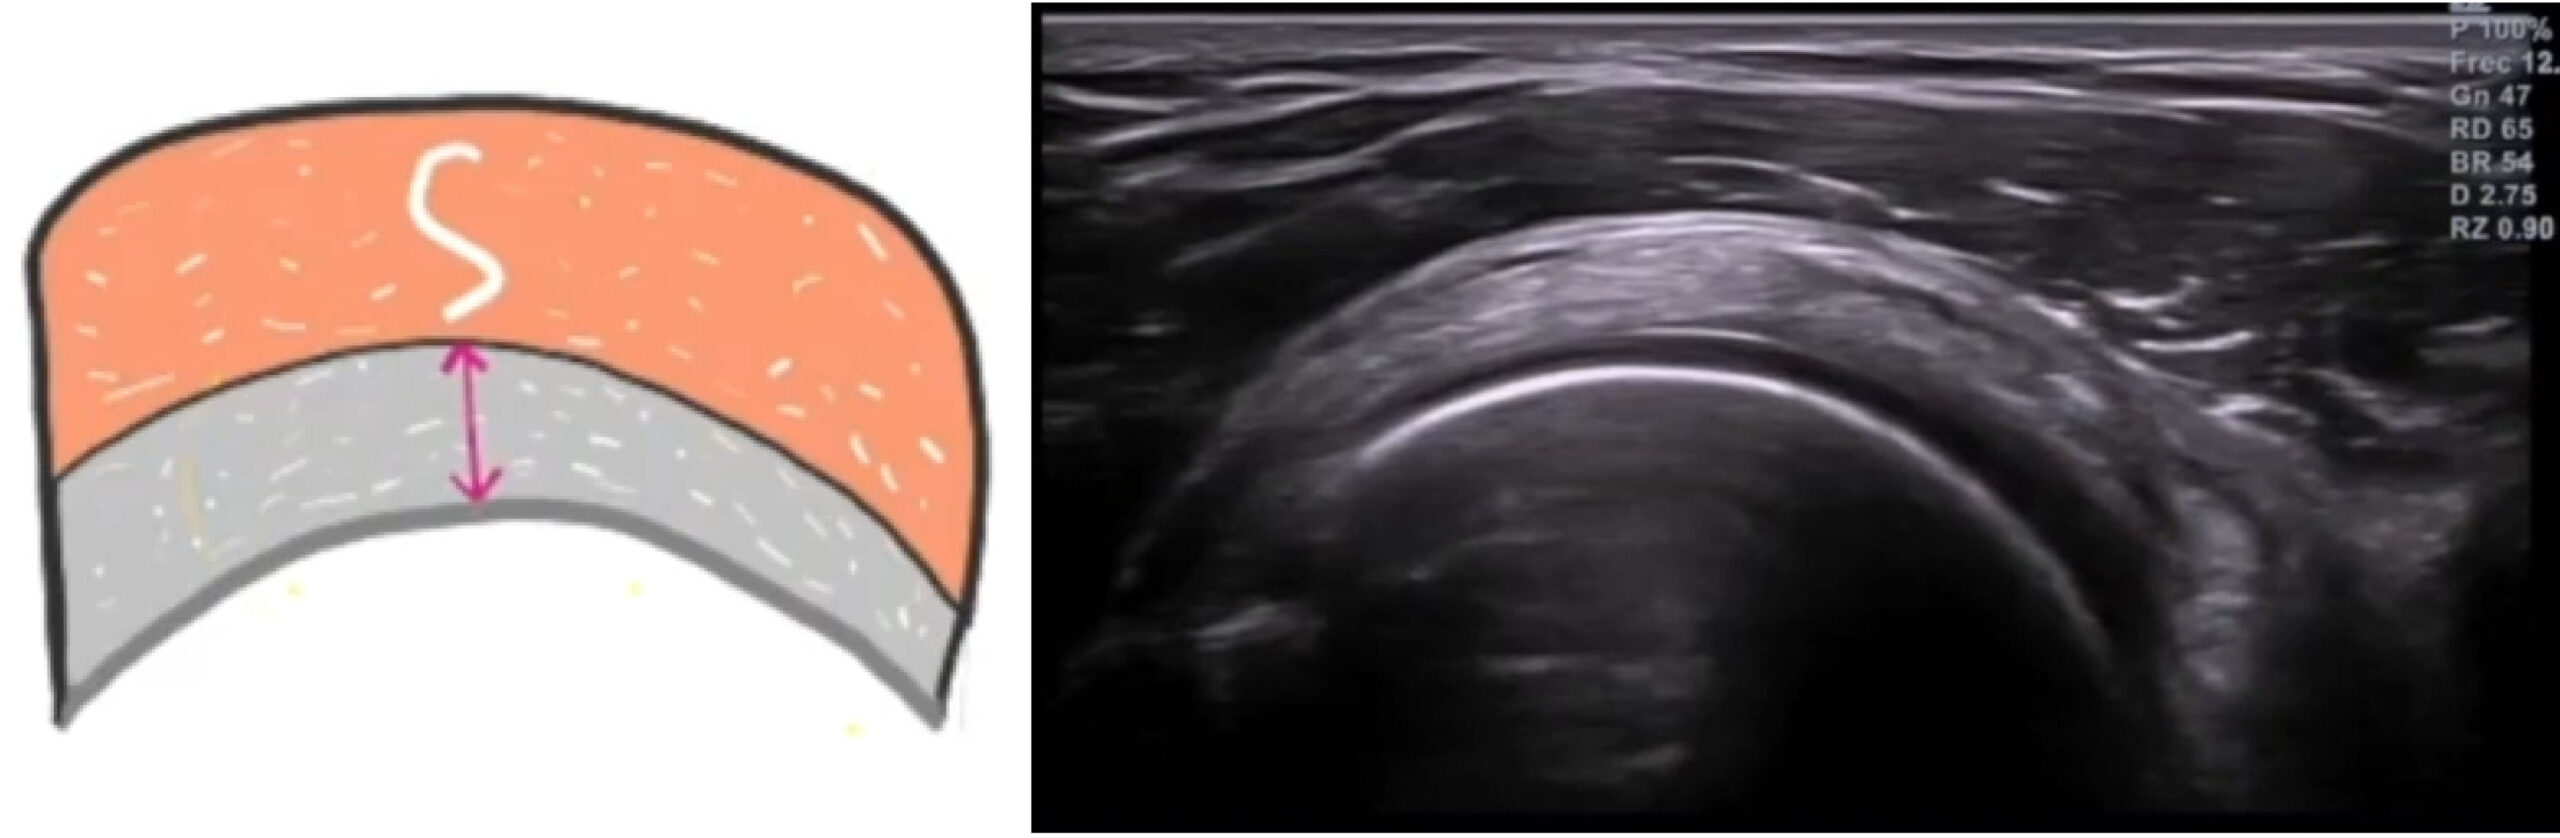

En eje longitudinal (corte largo): el tendón tiene una estructura fibrilar bien definida, hiperecoica, con líneas paralelas y continuas. La corteza ósea del troquíter se ve como una línea blanca y brillante. Por encima del tendón, la bursa subacromial-subdeltoidea aparece como una fina línea hipoecoica (no siempre visible en condiciones normales) y, por encima de esta, el músculo deltoides.

En eje transversal (corte corto): el tendón tiene un aspecto ovoide o semilunado, con ecogenicidad homogénea. Este corte es ideal para medir su grosor y comparar con el lado contralateral.

La interfase superficial del tendón suele ser más ecogénica que la profunda. Eso es normal.